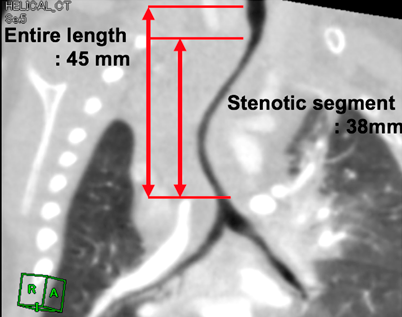

We evaluated the details of tracheal stenosis using CT (Fig. 1A) and calculated the stenotic segment ratio, which was estimated by the following formula (Fig. 1B, 1C)4): Normal tracheal lumen diametertracheal lumen diameter of the most stenotic part Normal tracheal lumen diameter We also calculated the longitudinal stenotic tracheal segment ratio as shown in Fig. 2. Long-segment tracheal stenosis was defined as the ratio of the stenotic tracheal segment to that of the entire tracheal length of >50%.5)

Fig. 1 Preoperative contrast CT

(A) The left PA originates from the posterior aspect of the right PA. (B) A sagittal view of patient No. 2 shows the tracheal diameter of the most stenotic part (distance between the red arrows is 2.3 mm). (C) Normal tracheal lumen diameter (distance between the red arrows is 4.7 mm). Des-Ao, descending aorta; LPA, left pulmonary artery; RPA, right pulmonary artery.